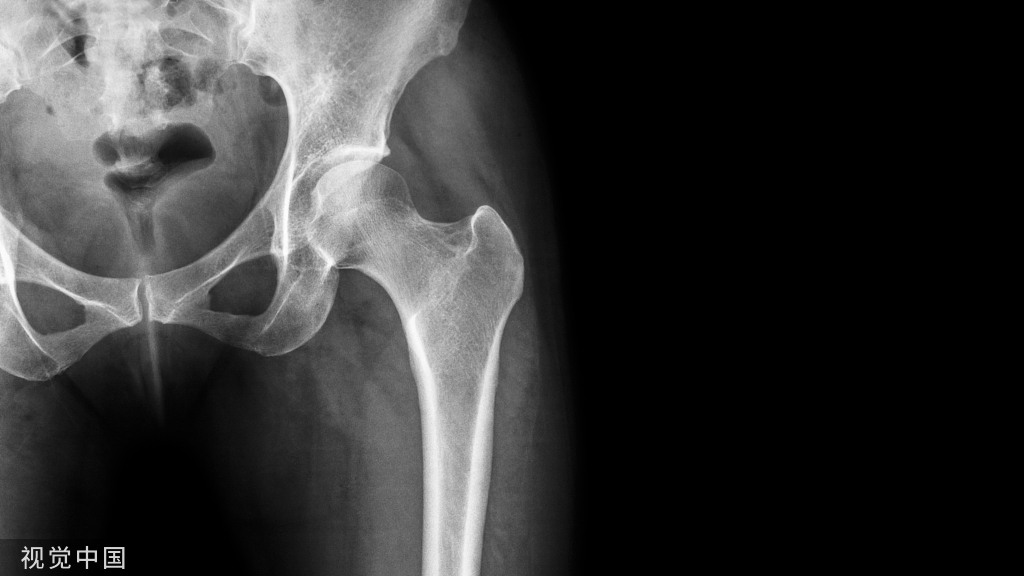

4个月后复查CBCT见充填物完好,根尖低密度暗影基本消失,根管长度较4个月前未见明显改变。